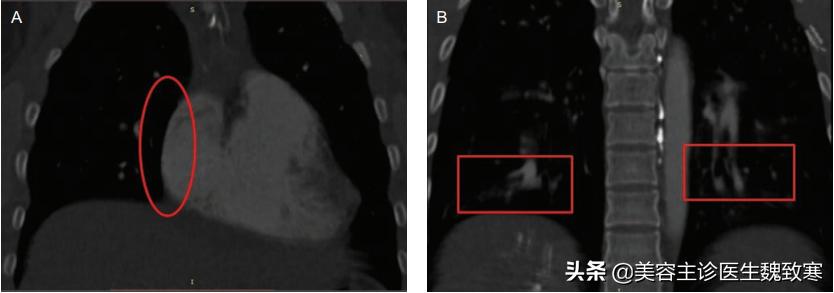

患者无吸烟或饮酒史,胸部听诊显示肺部大部分为双侧湿罗音。胸部计算机断层扫描(CT)显示左肺下叶局部渗出(见上图1),右心房(图2A)和心室增大,双侧下叶动脉发育不均伴充盈缺损(图2B)。

图2A、图2B

肺CT血管造影和三维重建显示右下叶后基底段肺动脉分支持续中断(图3)。经胸超声心动图显示心功能基本正常,无瓣膜异常。